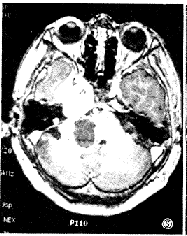

图3 同图1病例,注射Gd-DTPA后横轴位T1加权像显示中颅窝实性肿瘤呈均匀强化,后颅窝囊性肿瘤壁呈环状强化。

图4 右侧三叉神经鞘瘤。横轴位T1加权像显示肿瘤呈哑铃形骑跨于中后颅窝,呈混杂等或稍低信号,第四脑室受压变形,右岩骨尖骨质吸收。